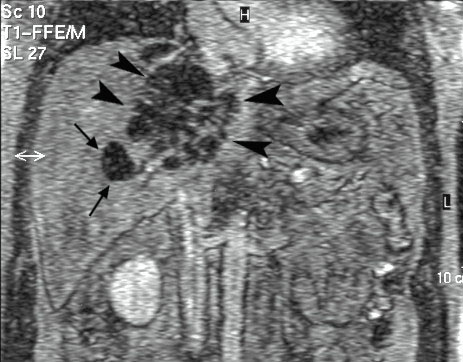

Even though Gemella morbillorum infection (GMI) is rare in humans, it may, nevertheless, cause endocarditis, meningitis, brain abscess, pleural empyema, nephritis, mediastinitis, and – occasionally – liver abscess. We are describing the case of a 64-year-old Caucasian male admitted with fever and abdominal pain. Laboratory parameters revealed inflammation signs, and instrumental examinations showed the presence of diverticula in the ascending colon. Abdominal ultrasound (US) and computer tomography (CT) showed two focal lesions in the right liver lobe. One had the characteristics of a simple cyst; the second was hypoechoic with a low density area, possibly containing necrotic material. US-guided needle biopsy was found negative for neoplastic cells, showing purulent infiltrate. Pus culture was found positive for GMI. Systemic antibiotic therapy, coupled with repeated US-guided needle aspiration, induced the resolution of the hepatic abscess. Few cases have been reported of hepatic abscess caused by GMI in immunocompetent non-cirrhotic subjects.Authors